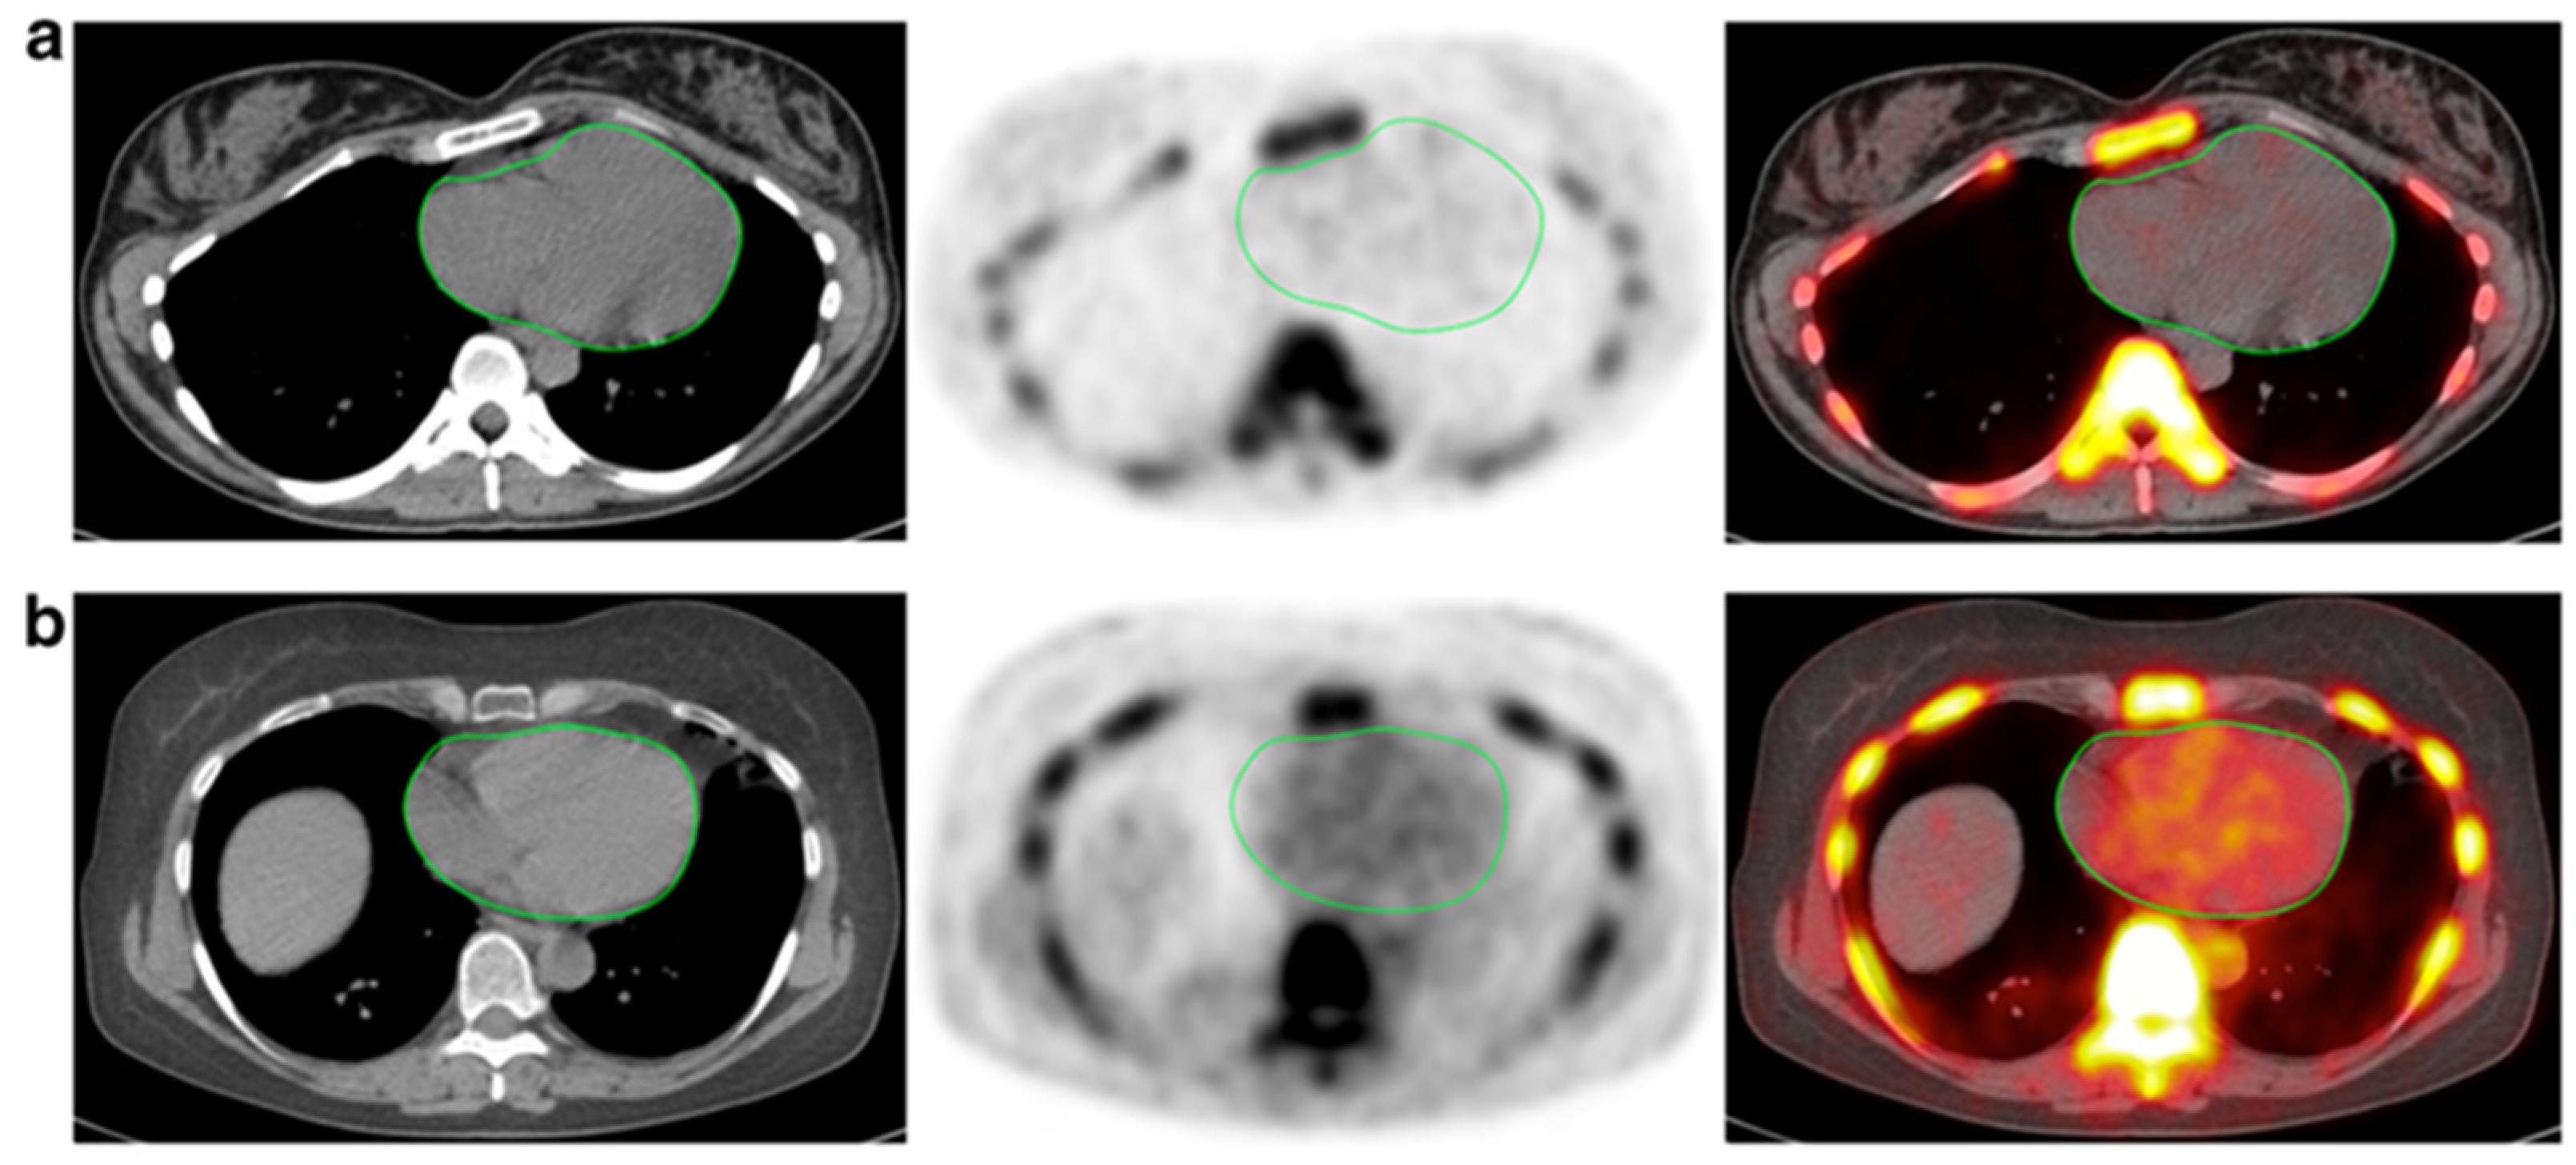

Figure 2.

CT, NaF-PET, and fused NaF-PET/CT images of clinically normal (a) 25- and (b) 61-year -old subjects’ hearts. Green line delineates the region of interest around the heart analyzed to calculate the global cardiac calcification scores, which are 12,492.44 (a) and 18,424.70 (b). Despite the relatively increased NaF uptake in the PET scan of the subject’s heart (b), there is no visible calcification in the corresponding CT scan. The disparity between two modalities alludes to CT-visible macrocalcification as end-stage disease process, while NaF uptake may reflect early pathological, molecular changes (from Raynor et al. [94] with permission).